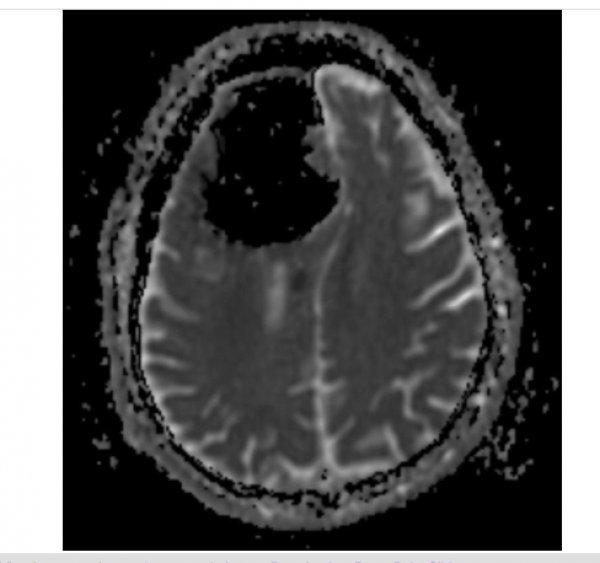

Doktorlar röntgene baktığında beynin sağ tarafında 9 santimlik siyah bir görüntü gördü. Doktorlar, 84 yaşındaki hastanın sağ ön lobunun olmadığını fark etti.

Doktorlar hastanın pnömatosel rahatsızlığı ( akciğerde kistik hava boşluğu) olduğu için beyin dokusuna zarar verdiği görüşünde birleşti.